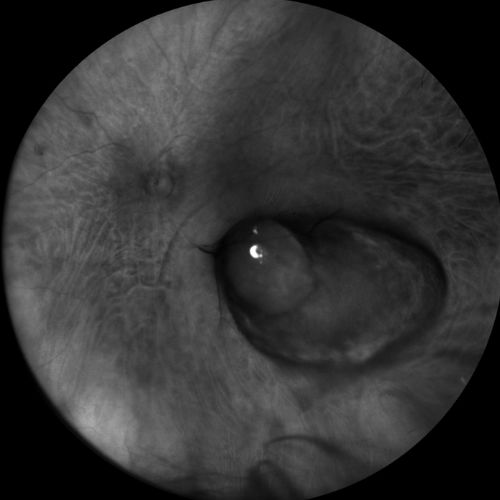

OCT

Ecografia A-B scan